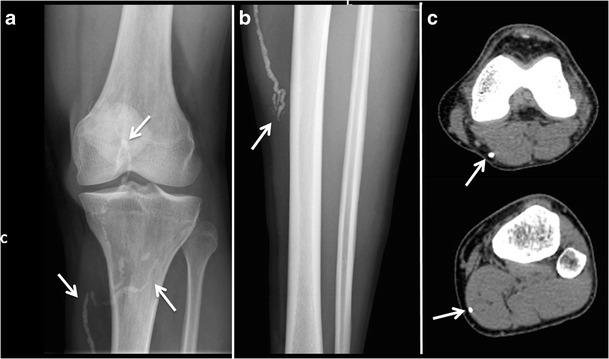

Radiologists seldom encounter parasitic diseases in their daily practice in most of Europe, although the incidence of these diseases is increasing due to migration and tourism from/to endemic areas. Moreover, some parasitic diseases are still endemic in certain European regions, and immunocompromised individuals also pose a higher risk of developing these conditions. This article reviews and summarises the imaging findings of some of the most important and frequent human parasitic diseases, including information about the parasite's life cycle, pathophysiology, clinical findings, diagnosis, and treatment. We include malaria, amoebiasis, toxoplasmosis, trypanosomiasis, leishmaniasis, echinococcosis, cysticercosis, clonorchiasis, schistosomiasis, fascioliasis, ascariasis, anisakiasis, dracunculiasis, and strongyloidiasis. The aim of this review is to help radiologists when dealing with these diseases or in cases where they are suspected. Teaching Points • Incidence of parasitic diseases is increasing due to migratory movements and travelling. • Some parasitic diseases are still endemic in certain regions in Europe. • Parasitic diseases can have complex life cycles often involving different hosts. • Prompt diagnosis and treatment is essential for patient management in parasitic diseases. • Radiologists should be able to recognise and suspect the most relevant parasitic diseases.

在欧洲大部分地区,放射科医生在日常工作中很少遇到寄生虫病,尽管由于往返于流行地区的移民和旅游活动,这些疾病的发病率正在上升。此外,某些寄生虫病在欧洲的某些地区仍然流行,免疫功能低下的个体感染这些疾病的风险也更高。本文回顾并总结了一些最重要且常见的人类寄生虫病的影像学表现,包括有关寄生虫生命周期、病理生理学、临床表现、诊断和治疗的信息。我们涵盖了疟疾、阿米巴病、弓形虫病、锥虫病、利什曼病、棘球蚴病、囊尾蚴病、华支睾吸虫病、血吸虫病、片形吸虫病、蛔虫病、异尖线虫病、麦地那龙线虫病和粪类圆线虫病。这篇综述的目的是在放射科医生处理这些疾病或怀疑患有这些疾病的病例时提供帮助。教学要点 • 由于人口迁移和旅行,寄生虫病的发病率正在上升。 • 某些寄生虫病在欧洲的某些地区仍然流行。 • 寄生虫病可能具有复杂的生命周期,通常涉及不同的宿主。 • 及时诊断和治疗对于寄生虫病患者的管理至关重要。 • 放射科医生应该能够识别和怀疑最相关的寄生虫病。